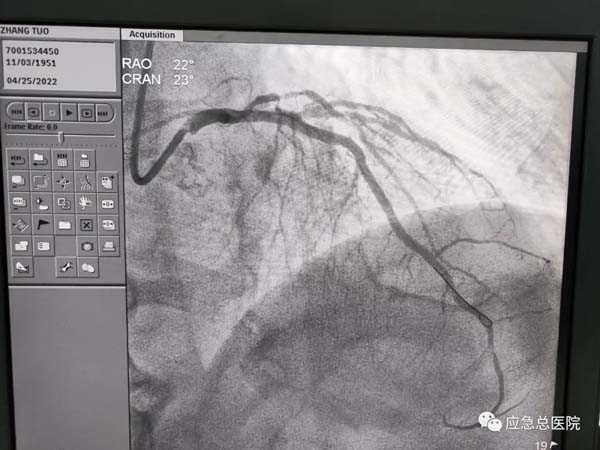

生命在接力。来到应急总医院后,为患者第一时间进行造影检查,结果提示:三支病变,前降支近端100%闭塞,也就是说供应心脏的三条血管均有严重的狭窄,而最主要的血管——前降支已经完全堵死,晚一点救治后果不堪设想。吴迪教授第一时间研判:务必马上开通闭塞血管,一刻都不能耽搁!因为应急总医院有一支经验丰富的介入团队,在吴迪教授的指导下,在范煜东副主任的熟练操作下,在张子龙副主任医师、张庆军主治医师及导管室护士、技师的通力配合下,病人的闭塞血管及时开通,如久旱甘霖般将鲜活的血液重新给濒临坏死的心肌细胞。手术一做完,病人就长舒一口气:“不疼了!舒服了!”在手术室门口焦急守候的家属,此刻喜极而泣。看看时间,从张大爷到光熙医院就诊,再转运到应急医院完成手术,仅用了50分钟。

手术后